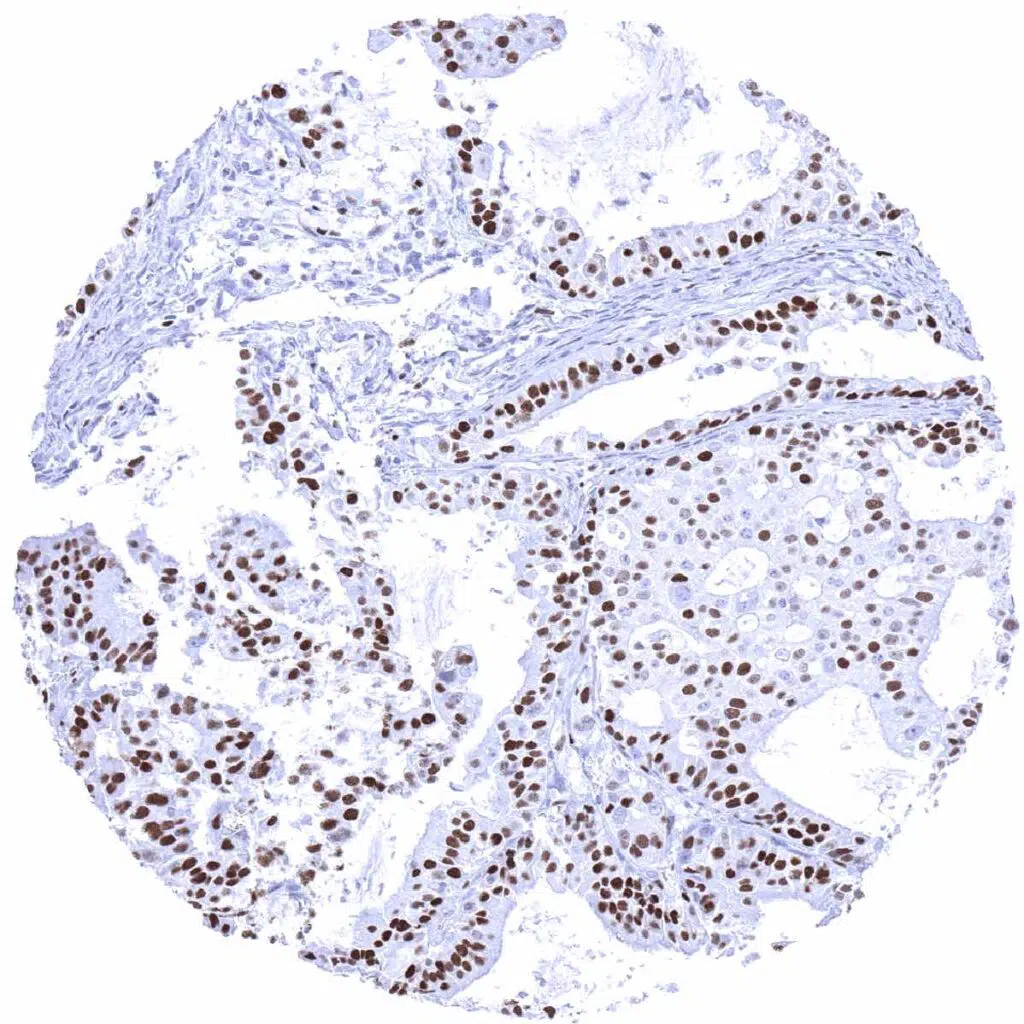

Pancreas- Ductal adenocarcinoma with MCM7 staining of a fraction of tumor cells